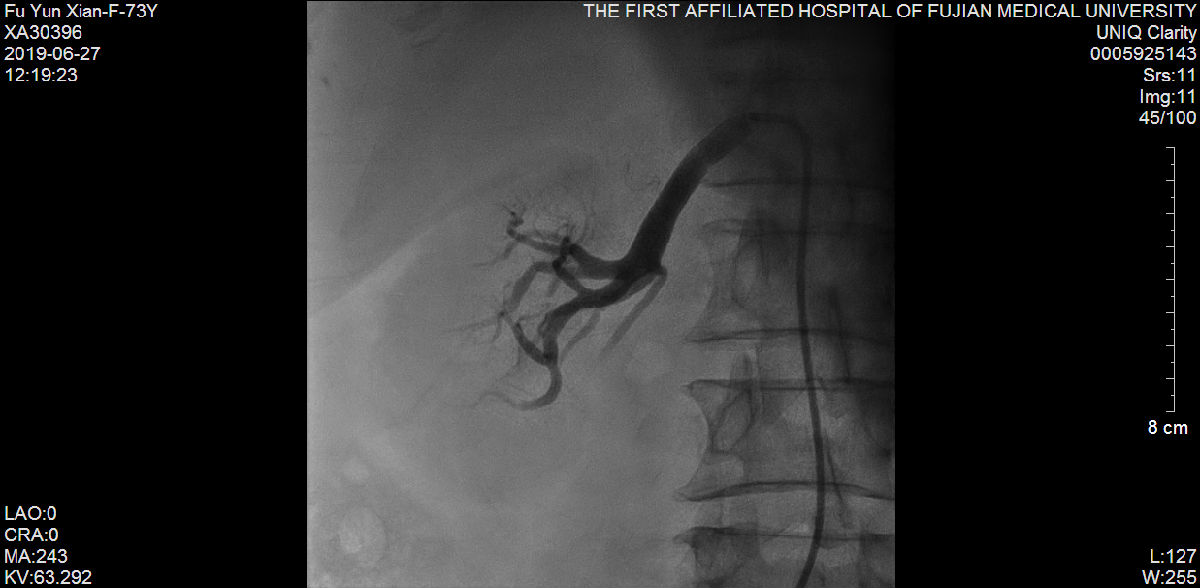

随后,苏津自教授、蔡瀚医师为傅阿姨进行介入手术:肾动脉造影显示双侧肾脏萎缩,右侧肾脏具备进行RDN的条件;而冠状动脉造影显示营养心脏的其中一条主干血管——前降支血管近端99%狭窄伴冠状动脉瘤样扩张。